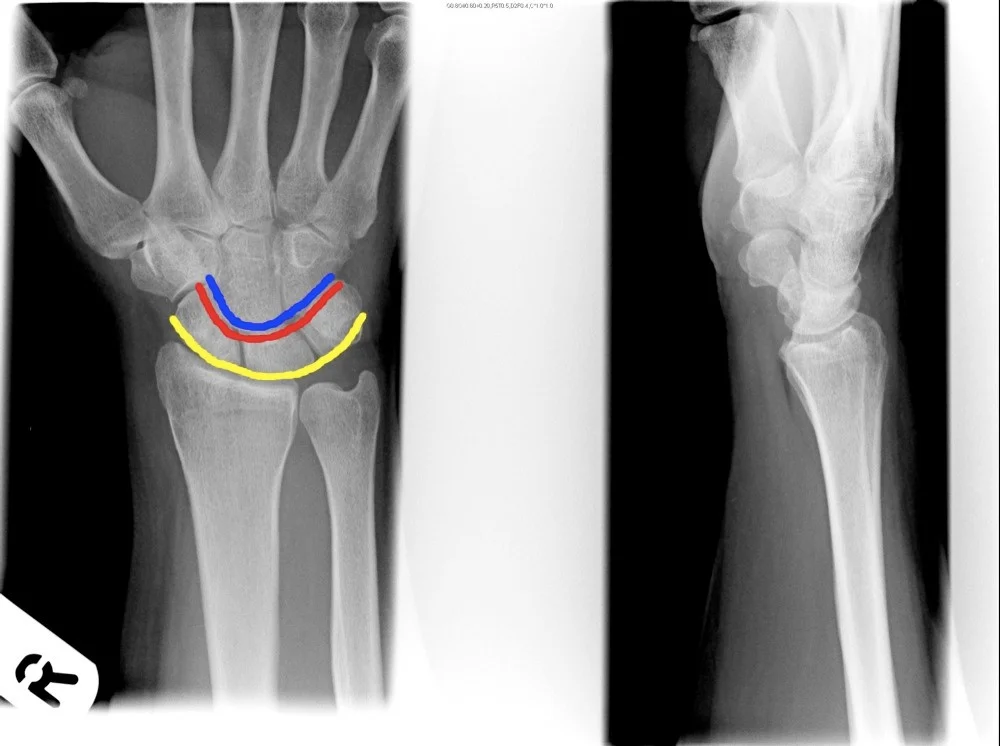

Follow the Cortex

- x-ray of wrist undisplaced fracture of scaphoid

- In Trauma â âFollow the Cortexâ â adjust brightness/contrast to reveal the fracture line.

Patient: 62âyearâold man

-

Mechanism of injury: slipped at the carpet edge and fell on an outstretched hand, resulting in wrist pain and swelling

Fracture details

- Site: distal radius

- Type: simple, transverse, extraâarticular

- Displacement: dorsal tilt of ~20°

Special considerations

- Osteoporosis/penia (reduced bone density)

- Collesâ fracture (classic distal radius fracture pattern)

A 29âyearâold man fell from a ladder and presents with pain in the wrist.

- Site â wrist

- Type â (Specify fracture type)

- Fracture line â (Describe orientation)

- Displacements â (Note any displacement)

- Special issues â (Highlight any neurovascular or softâtissue concerns)

A 37-year old man fell from a down the stairs, C/O pain at wrist ⢠Site ⢠Type ⢠Fracture line

- Displacements

- Special issues

- Site

- Type

- Fracture line

- ⢠Site

- ⢠Type

- ⢠Fracture line

- ⢠Displacements

- ⢠Special issues